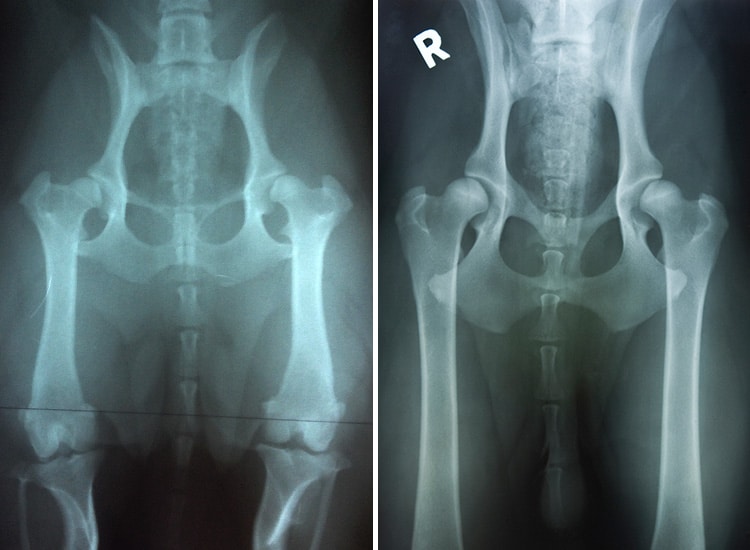

Le diagnostic de la dysplasie de la hanche est généralement effectué grâce à un examen clinique et radiographique.

Lors de l’examen orthopédique, le vétérinaire recherche une douleur, une diminution de l’amplitude articulaire, une laxité anormale de la hanche ou encore une gêne lors des manipulations. Les radiographies permettent ensuite de confirmer le diagnostic, de visualiser une éventuelle subluxation et d’évaluer l’importance de l’arthrose.

Radiographies de dysplasies bilatérales de la hanche chez deux chiens de 12 et 14 mois

Dans certaines races de chiens, un protocole standardisé de dépistage est imposé pour la confirmation de tout chien dans le Livre Officiel Français (LOF), ceci afin d’exclure les individus touchés par cette affection de la reproduction.